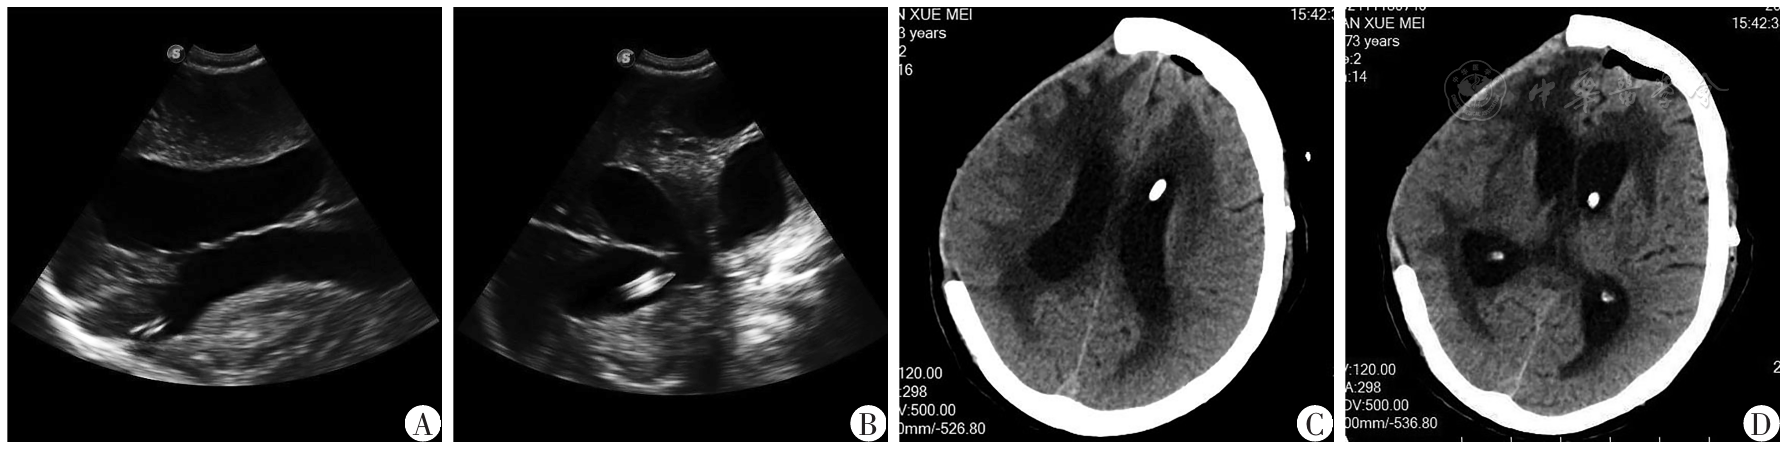

图2 去骨瓣减压术后合并脑积水患者行多模态辅助脑室-腹腔分流术术中实时引导脑室端超声及术后CT影像A:术中超声引导分流管头端进入侧脑室;B:术中超声引导分流管头端到达侧脑室室间孔附近;C:术后第2天CT示分流管进入脑室位置;D:术后第2天CT示分流管头端位于脑室室间孔附近

Fig.2 Real-time ultrasound guidance for intraventricular catheter placement and postoperative CT imaging during multimodal-assisted ventriculo-peritoneal shunt surgery in patients with hydrocephalus following decompressive craniectomy